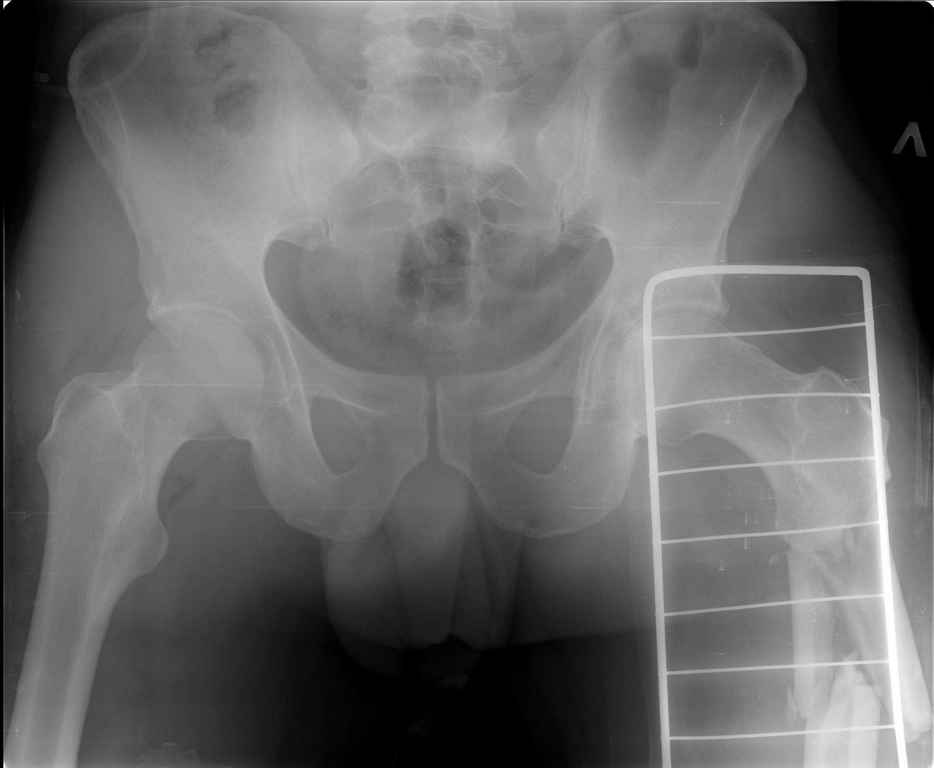

состоянии. Ds: ТСТ. ЗЧМТ. СГМ. ЗТГК. О/фрагментарный перелом левого бедра. З/оскольчатый

перелом с\3 левого плеча. Перелом левого локтевого отростка. З/перелом наружного мыщелка

выявлено вторичное смещение дистального отломка. Левая нога по сравнению со здоровой

удлиннена до 2,5см( это за счет вальгусной установки гвоздя в проксимальном отделе, боялся

свалиться на варус).